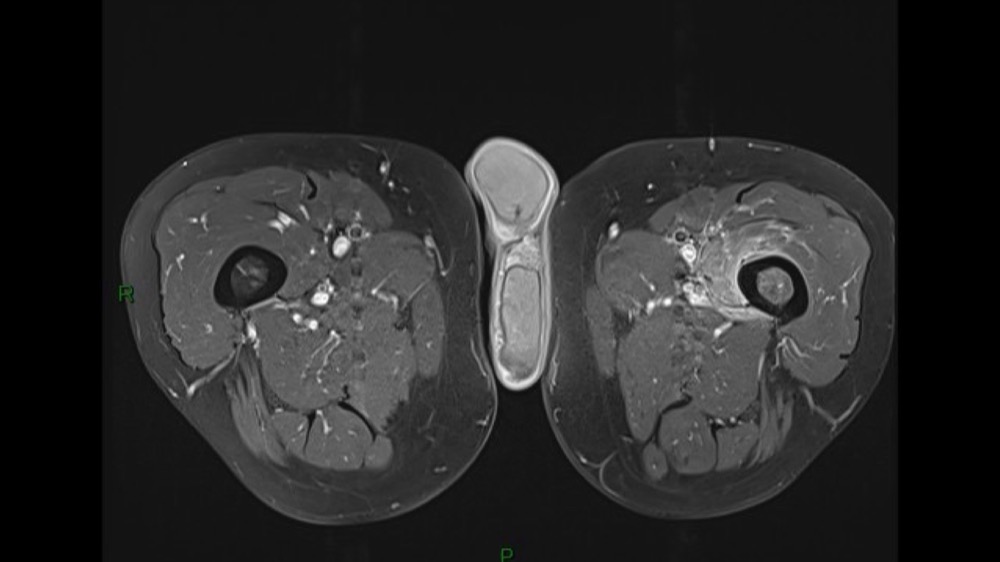

Lombo-cruralgie subaiguë trompeuse

Pascalie Jallerat 22/06/2020